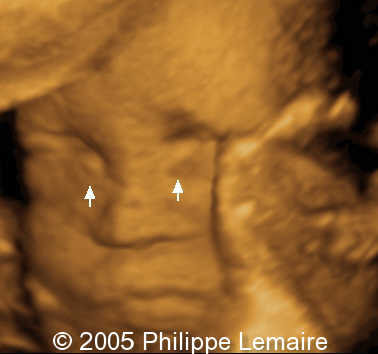

Dacryocystocele, 3D rendering

This is  a 3D-scan of bilateral dacryocystocele.